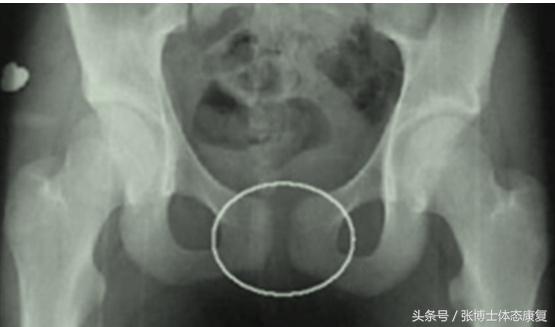

耻骨联合分离症的诊断

1、测试:耻骨局部有压痛和叩击痛,髋关节在做外旋外展时出现活动受限,进行耻骨联合加压和骨盆的挤压分离试验出现阳性体征

2、触诊:耻骨联合分离严重者,可触摸到分离的间隙

3、影像学检查:正常人耻骨间隙为4~6mm,孕期可增宽2~3mm。影像学X线片见耻骨联合间距离增宽,一般认为耻骨联合间隙超过10mm可确诊